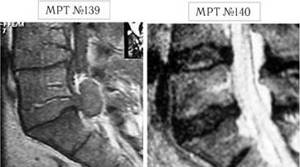

На МРТ поясничного отдела позвоночника №140 визуализируется состояние после оперативного лечения рецидивирующей грыжи и стеноза спинномозгового канала.

На МРТ поясницы №146 прослеживается секвестр за счет отделения хрящевой части диска. Осложнение состояние – разрыв продольной связки позвоночника